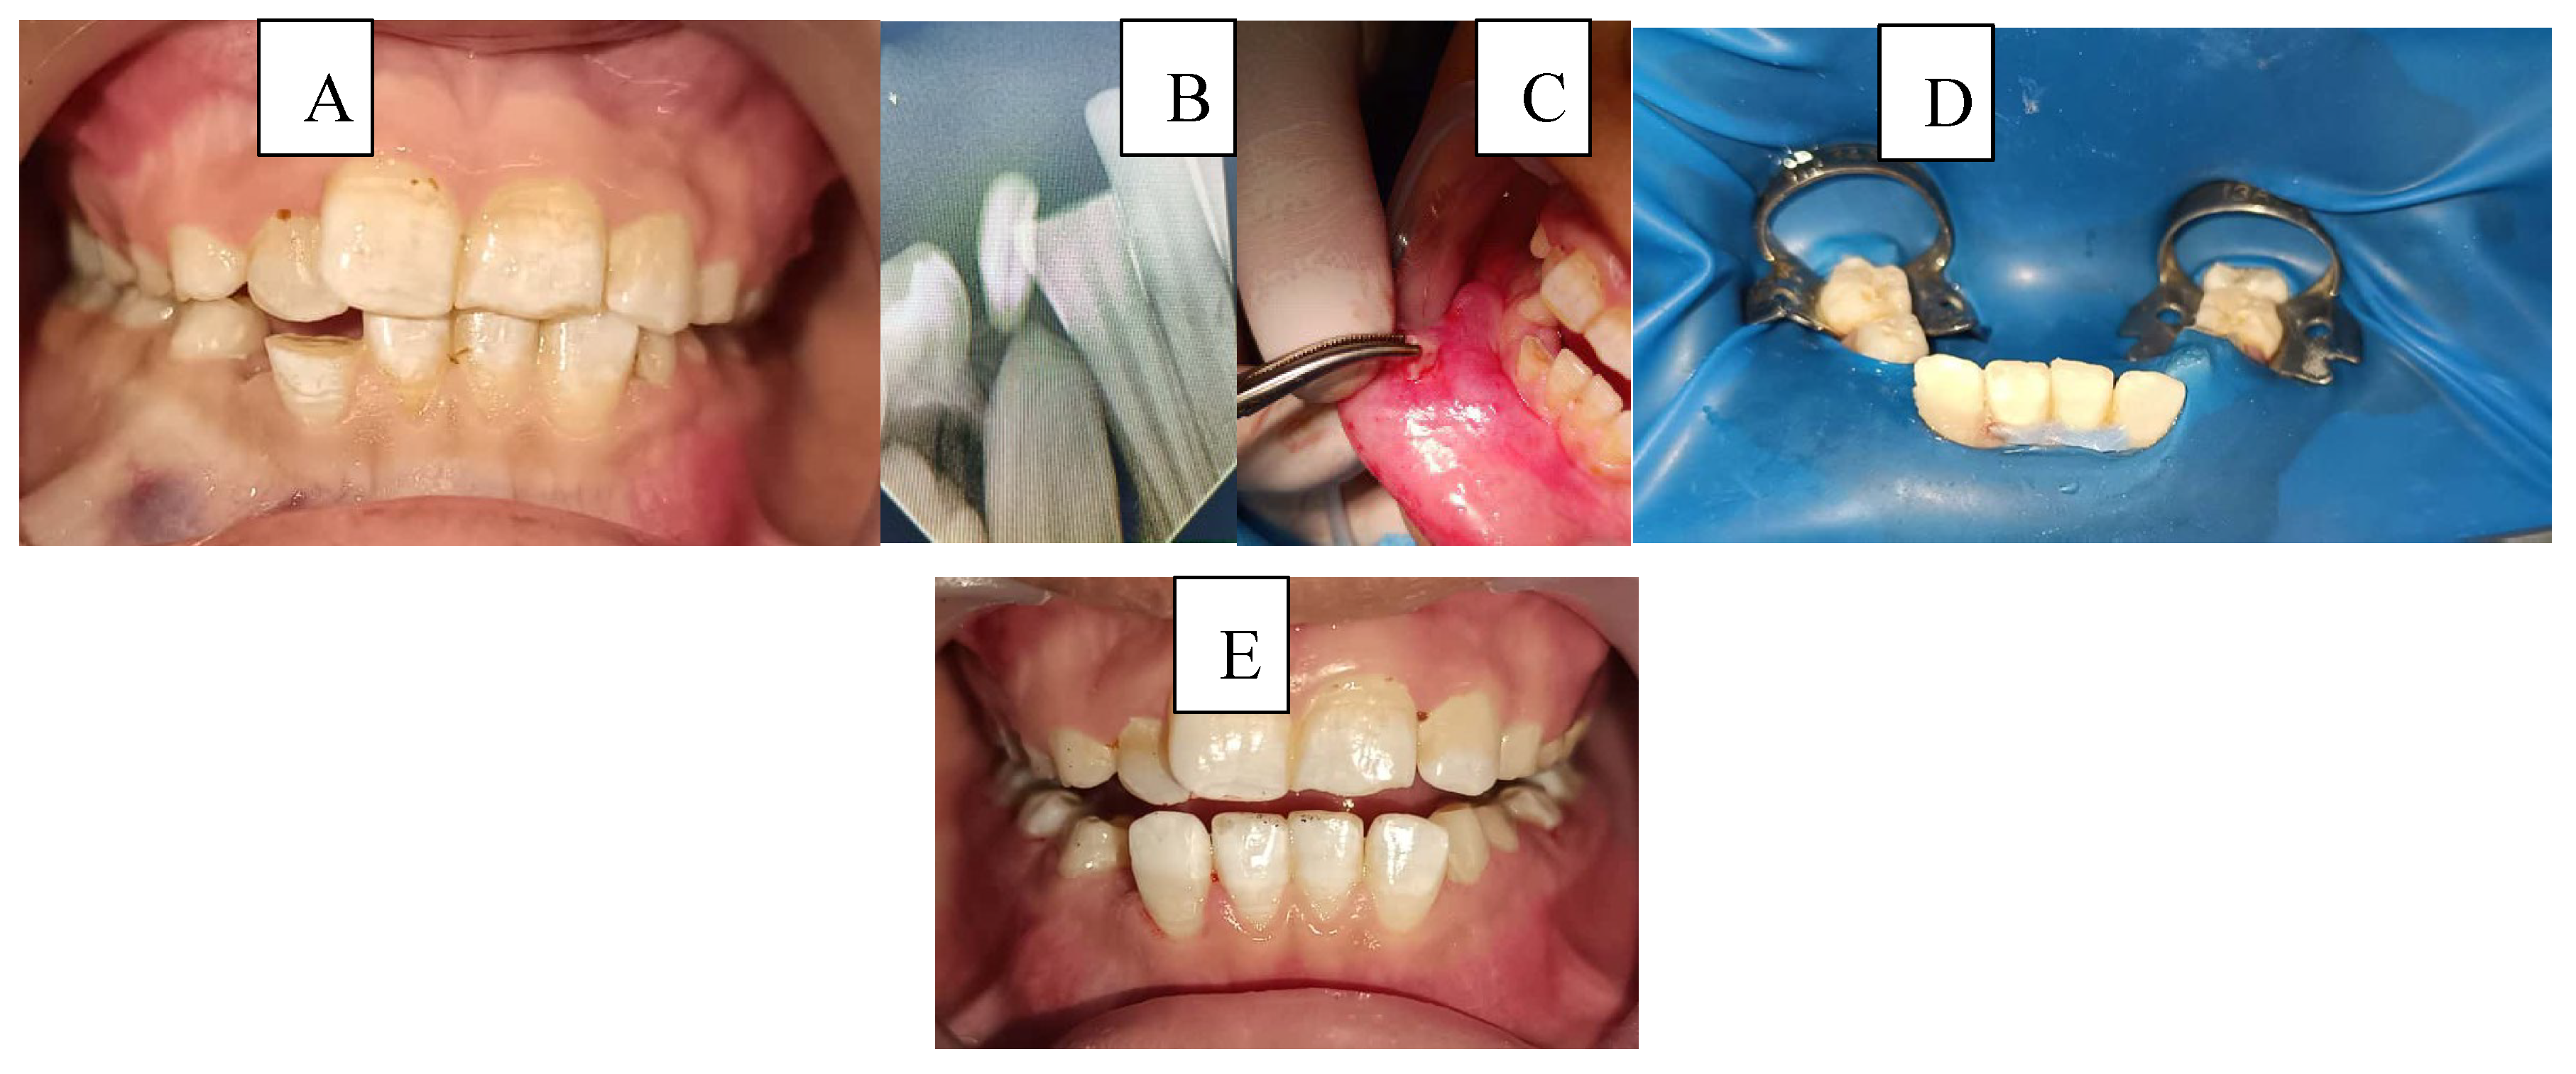

Figure 4. A case of managing a complicated crown fracture with the fractured fragment retained within the lower lip: A: Preoperative view, B: Radiograph showing the location of the broken fragment within the lower lip, C: Surgical removal of the fractured fragment, D: Isolation, endodontic treatment, and reattachment of the broken fragment in a single visit, and E: 6 months follow-up.

Case 2:

A 7-year-old child presented to the Department of Pediatric Dentistry three days after the injury with a complicated crown fracture involving pulp exposure in tooth #42. Radiographic examination revealed that the fractured crown fragment was embedded within the lower liAs the tooth had a closed apex, the fragment was surgically removed from the lip, followed by traditional endodontic treatment of tooth #42 in the same visit. The fractured crown segment was then successfully reattached to restore the tooth’s original form and function.